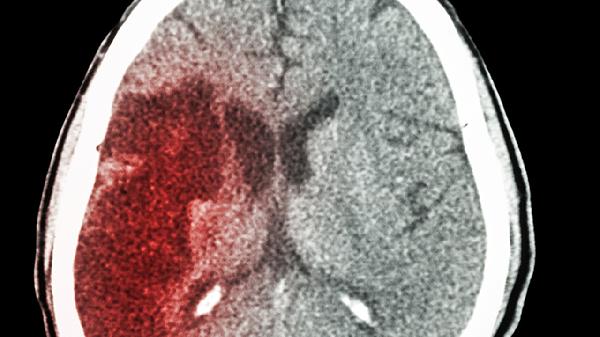

早期脑梗的症状主要有突发单侧肢体无力、言语含糊不清、短暂性视力障碍、头晕伴平衡失调、不明原因剧烈头痛等。脑梗即缺血性脑卒中,是脑部血液供应障碍导致的局部脑组织坏死,早期识别症状对及时救治至关重要。

早期脑梗常表现为突发单侧上肢或下肢无力,可能伴随面部肌肉下垂。这种无力感通常突然出现且持续存在,与疲劳或姿势压迫无关。患者可能出现持物不稳、行走拖步等症状,严重时完全丧失活动能力。该症状与大脑运动功能区供血不足有关,需立即就医进行头颅CT或MRI检查。